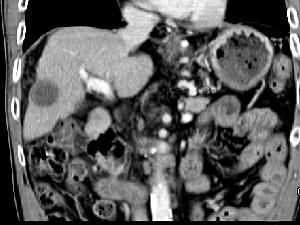

问题 男,63岁,肝区疼痛不适一个月,皮肤巩膜无黄染,AFP高于正常,CT所见如图,最可能的诊断是 ( )

选项 A.肝血管瘤 B.肝转移瘤 C.阿米巴肝脓肿 D.不典型肝癌 E.胆管细胞癌

答案 D